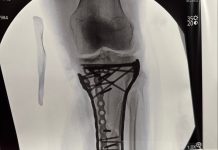

Ignorar las rutinas preventivas puede tener consecuencias severas: la pérdida de estabilidad articular impide competir con seguridad, y intentar esquiar con un ligamento cruzado anterior debilitado incrementa la probabilidad de lesiones complejas. En casos graves, la cirugía o una rehabilitación extensa pueden ser necesarias para recuperar la funcionalidad y evitar recaídas.